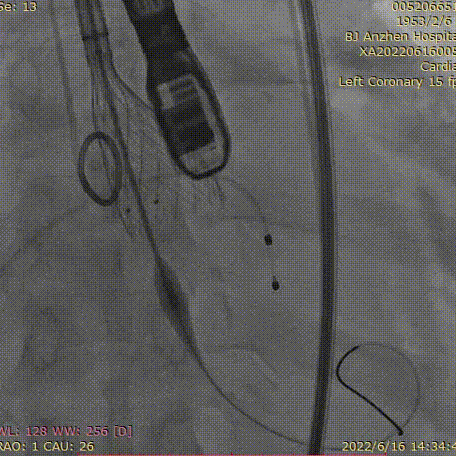

降主动脉造影

主动脉根部造影及调整机位

冠状动脉造影

13点35分,准备工作就绪,在宋光远教授带领下,手术团队迅速而有条不紊的完成股动静脉穿刺、置入鞘管、安置临时起搏电极、主动脉窦造影、导丝跨瓣、冠脉造影等一系列操作。接下来就要对患者狭窄的主动脉瓣进行球囊扩张,这是手术中风险很高的步骤,因球囊扩张时需要快速起搏心室,而患者心功能储备差,短暂的起搏也可能造成循环崩溃;所以需要整个手术团队密切配合,以确保万无一失。